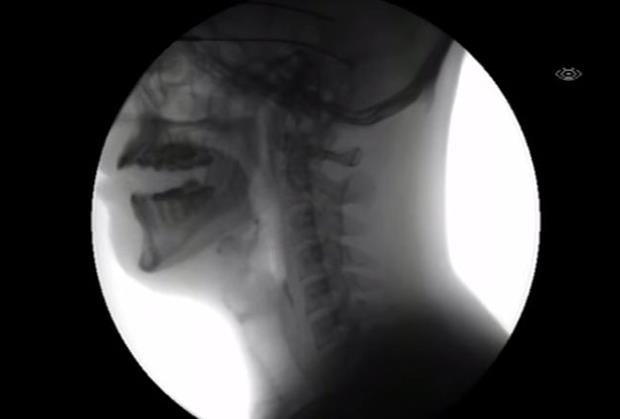

Jeste li se ikada zapitali šta se odvija u našim telima dok jedemo? Iako se čini da je reč o jednostavnim radnjama, rendgenski snimak pokazuje nešto potpuno drugačije.

I gutanje i žvakanje su složeni refleksni pokreti, a ovi refleksi potiču iz produžene moždine.

Žvakanje predstavlja mehanički deo u obradi hrane i obavlja se naizmeničnim podizanjem i spuštanjem donje vilice. Žvakanje spada u voljne radnje koje bez prekida kontroliše kora velikog mozga.

U procesu gutanja, zalogaj se premešta iz usta u želudac nizom pokreta. Nakon žvakanja nastaje zalogaj (bolus) i tek tada počinje proces gutanja koji se sastoji od nekoliko faza.